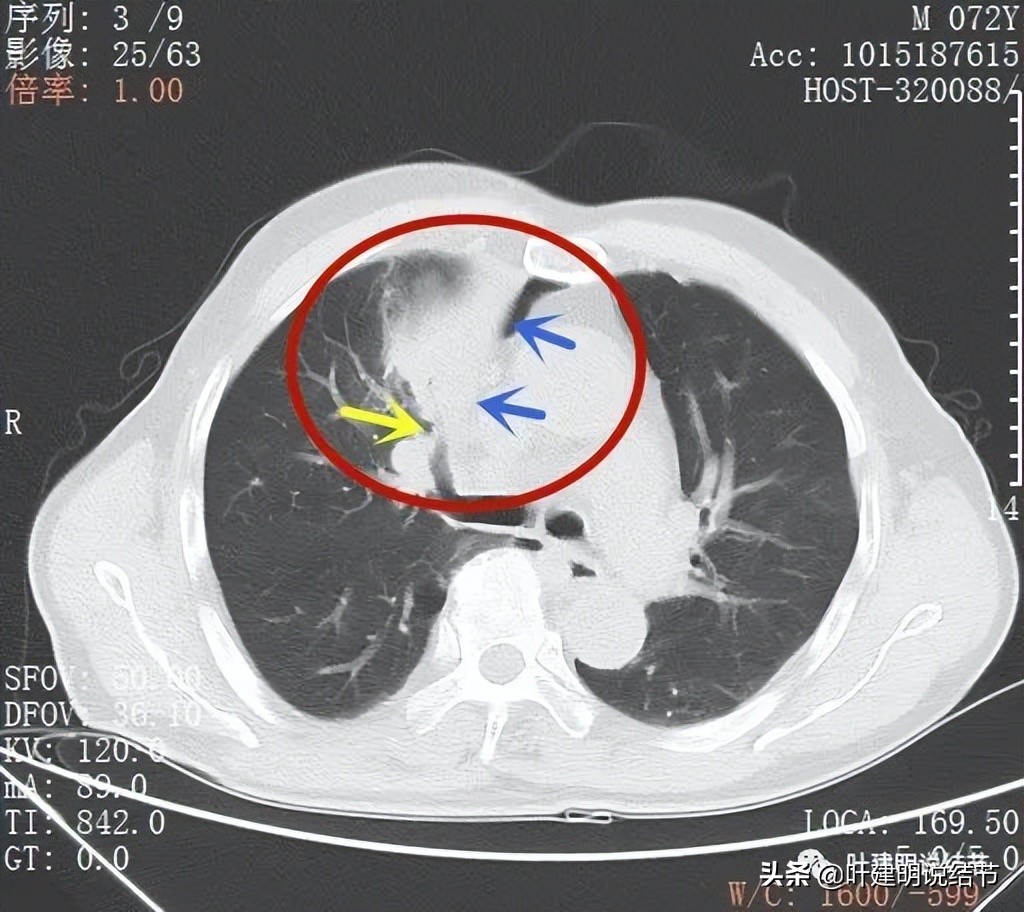

支气管似乎没有明显被侵犯或压迫(黄色箭头),边缘平滑(蓝色箭头)

上叶前段支气管(黄色箭头),病灶边缘缺乏膨胀性(蓝色箭头)